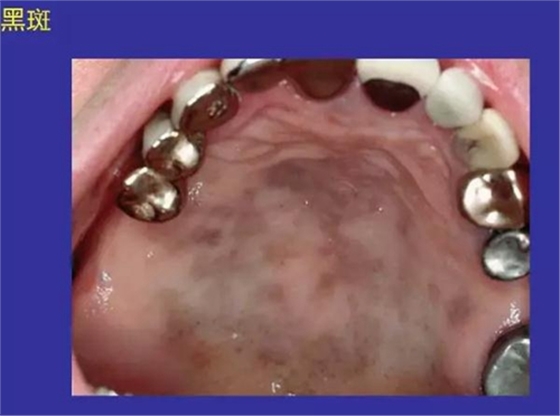

1.斑:黏膜上局限性顏色改變。

紅斑:赤斑、壞血病

黑斑:阿狄森病、色素沉著、陳舊性出血